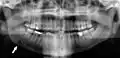

Панорамная рентгенограмма, показывающая дефект Стафне (отмечен стрелкой)